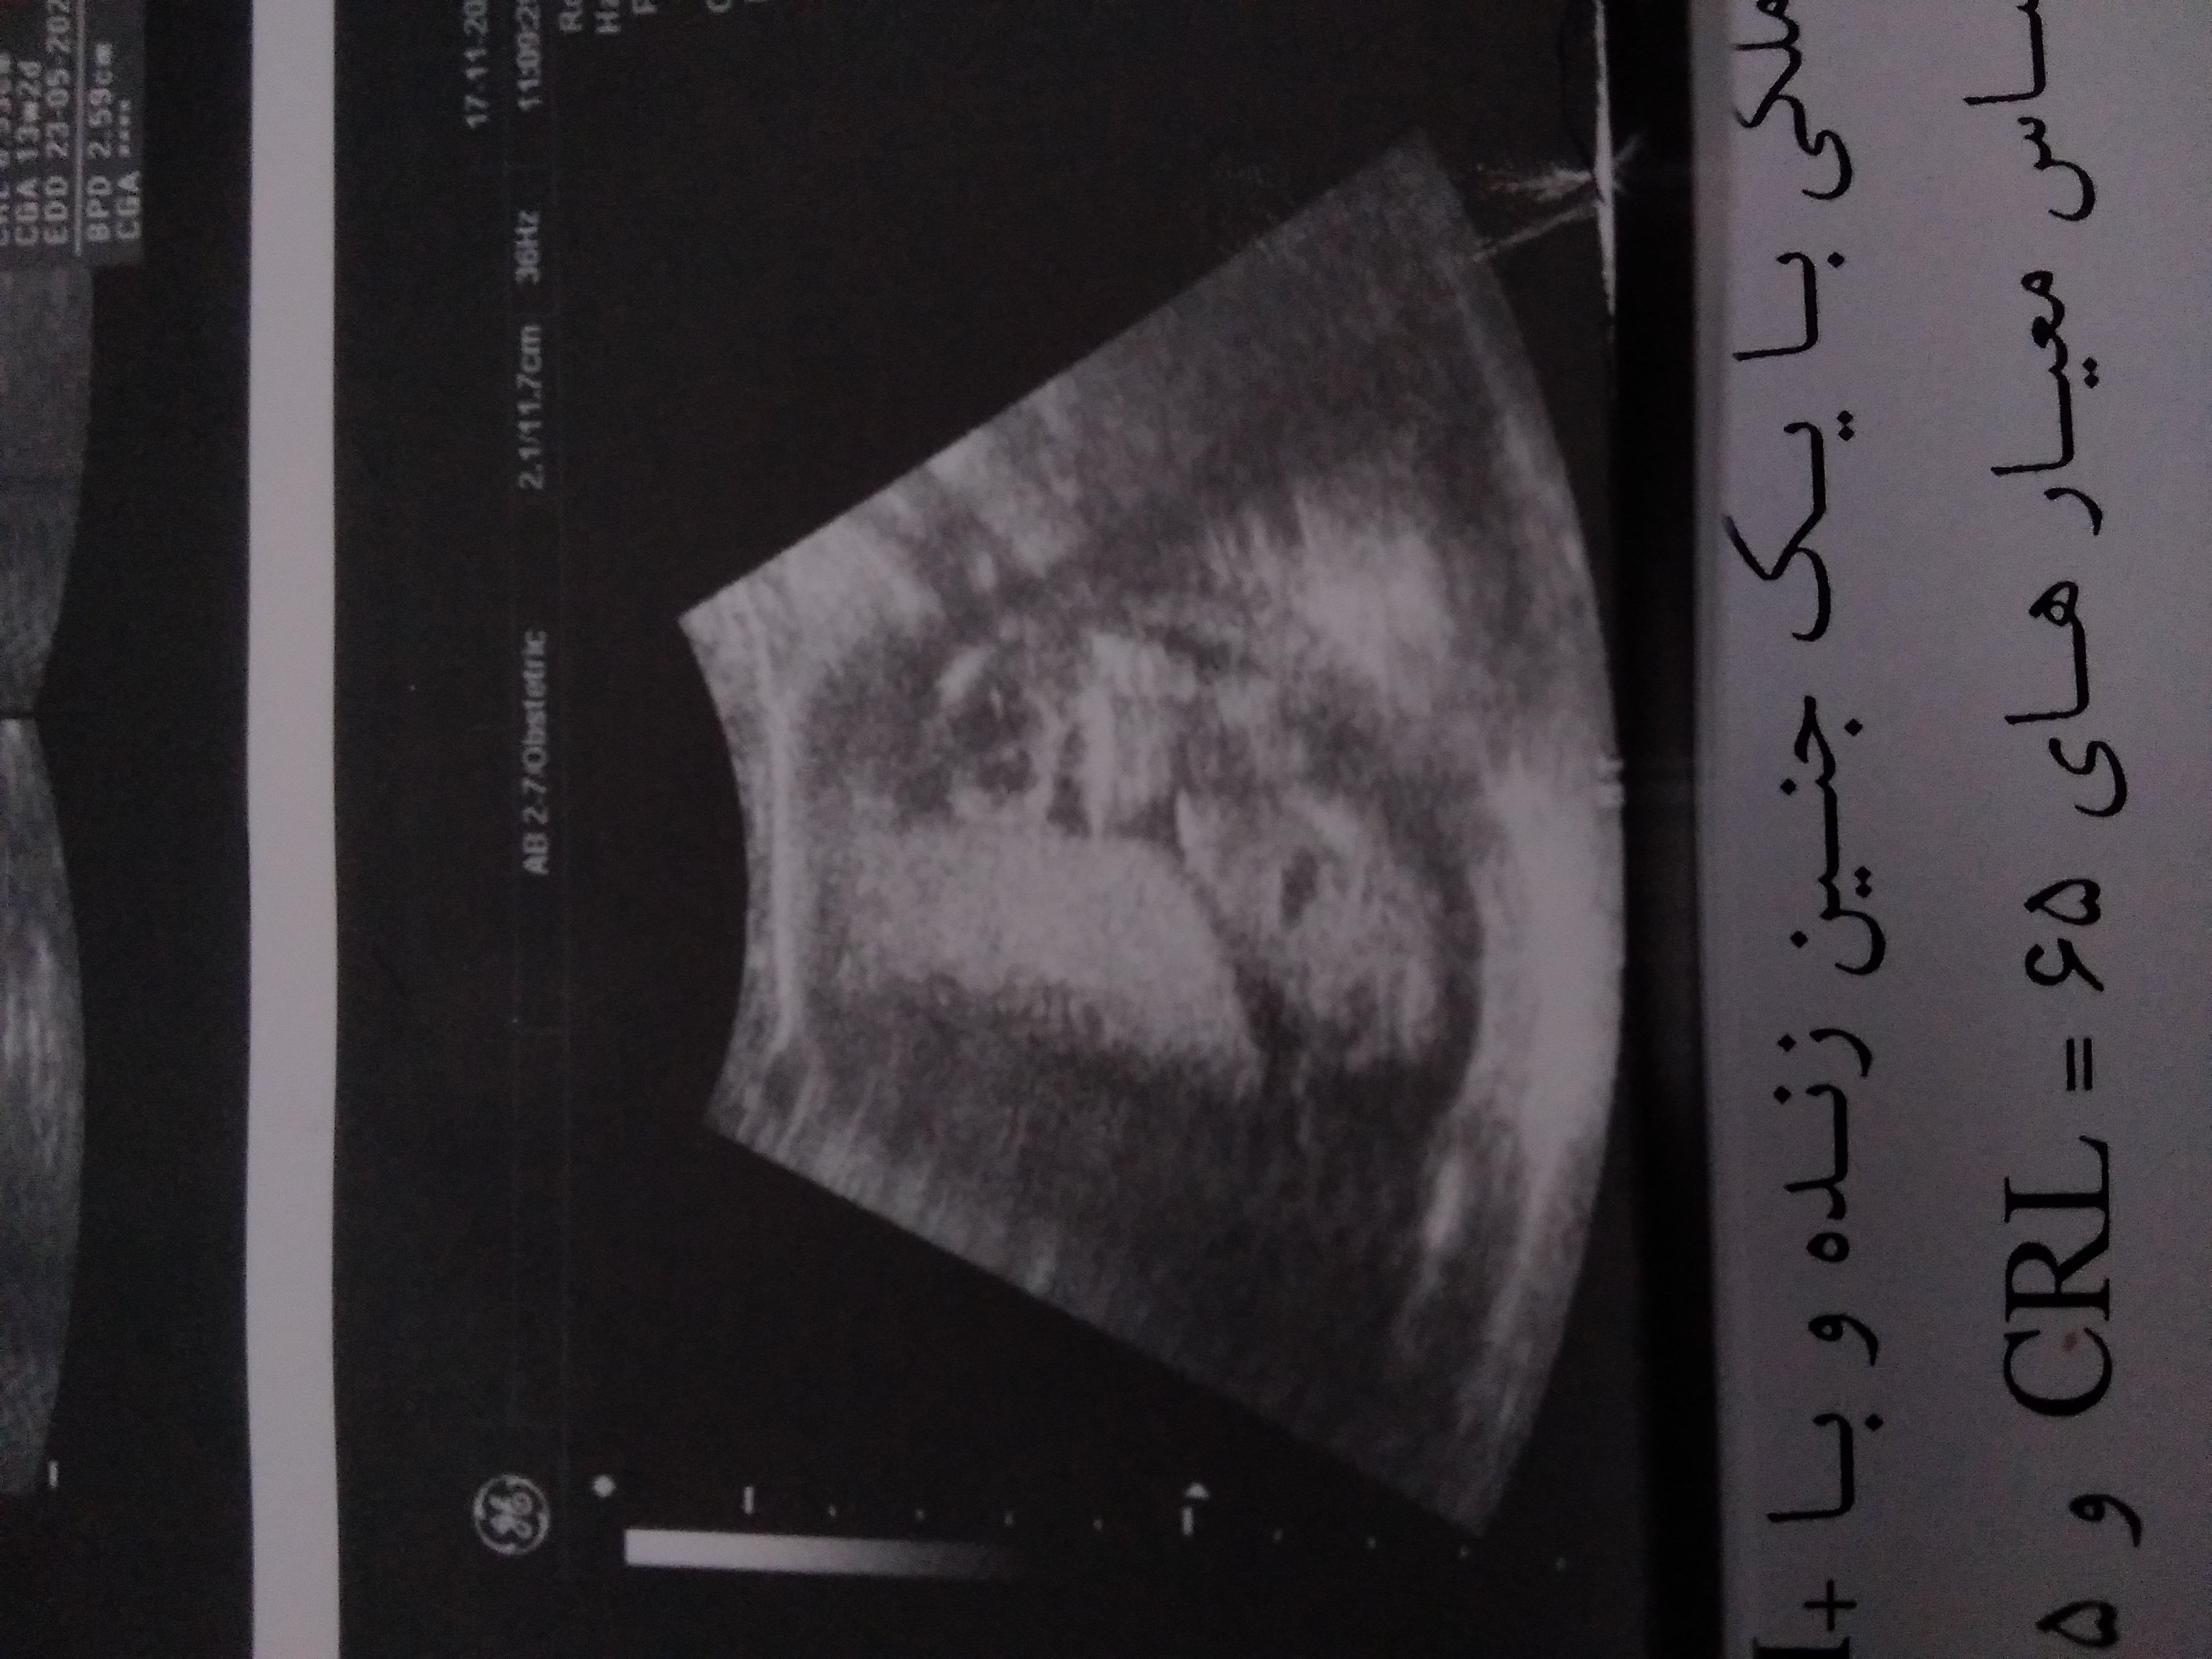

جون تو این عکس برآمدگی آلت تناسلیش خیلی معلوم نیست که با توجه به زاویه اش بشه بهتر تشخیص داد

عزیزم من فقط همینو دارم اره خودمم چیزی از الت تناسلی نمیبینم.۱۱ هفته و۵ روزم بوداخه.ضربان قلبشم ۱۵۸ بود بچه ام طرف راسته.ممنون خداکنه حدست درست باشه میام میگم ماه دیگه باید برم